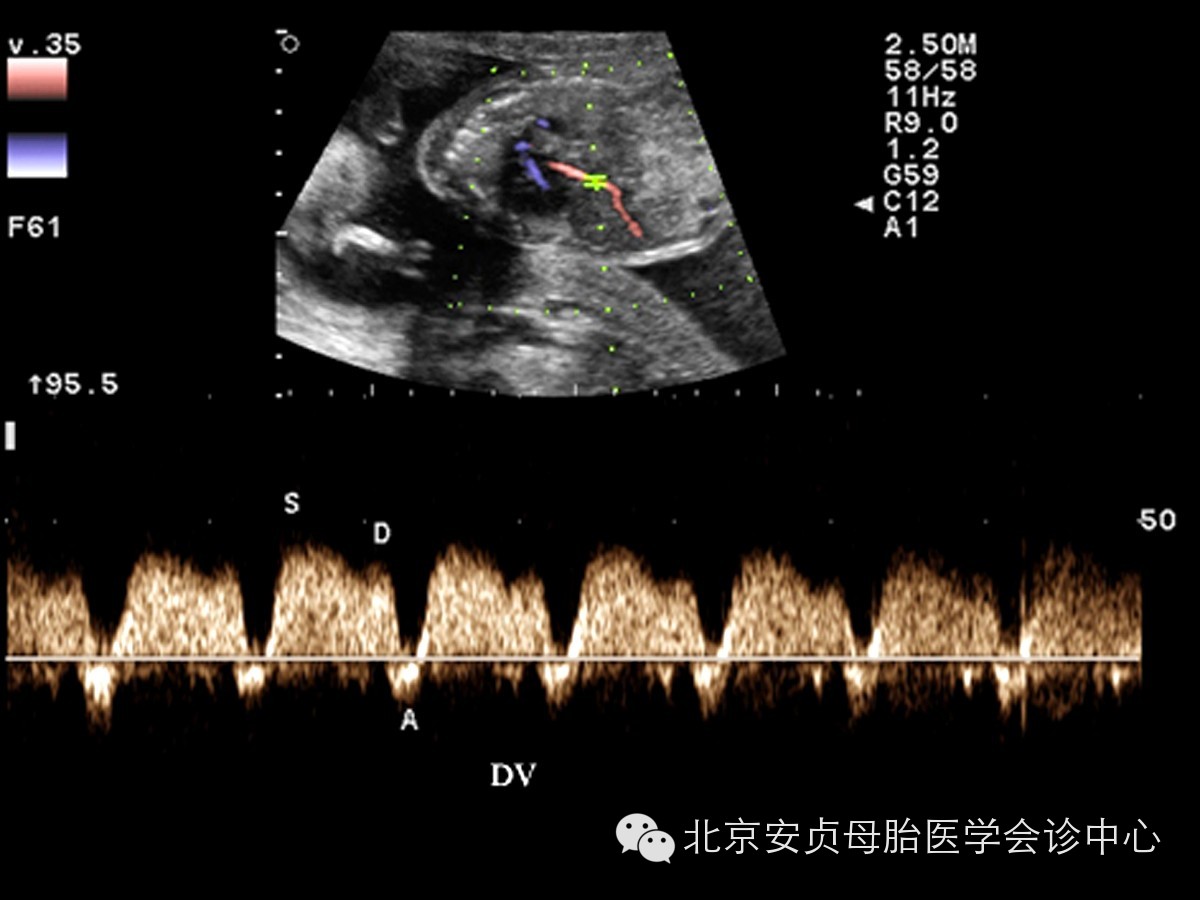

胎儿静脉血流能够客观、非特异性的用于评价心脏功能。对静脉系统频谱波形的分析主要包括:近心水平的静脉导管、下腔静脉、肝静脉、肺静脉;远心水平的腹内段脐静脉。与心房紧密相关的近心端静脉血流频谱正常均表现为多相血流波形。远心端脐静脉表现为无波动性的、低阻力连续静脉频谱波形。当上述静脉系统波形异常时,表明胎儿心脏舒张或收缩功能异常、心脏后负荷增加。

胎儿超声心动图阳性所见:左侧胎儿未见明显异常。位于右侧胎儿超声阳性所见:心脏位置正常,心脏增大,心胸面积比为0.43。左室横径18.3mm,左房横径16.3mm,右室横径17.2mm,右房横径22mm。房、室及大动脉连接关系正常。左、右室壁厚度未见异常,运动幅度明显减低。CDFI:左冠状动脉内血流信号显示清晰,流速1000cm/s,但各心腔内未见明确异常分流信号。心脏十字交叉结构存在,二尖瓣、三尖瓣瓣叶增厚,开放幅度减低。CDFI:收缩期二尖瓣房侧见少量反流信号,三尖瓣房侧见大量反流信号,TRVmax:7500cm/s,PGmax:36mmHg。肺动脉瓣增厚,回声增强,未见明显瓣膜启闭活动。CDFI:肺动脉内为源自动脉导管逆灌注血流信号。静脉导管频谱A波深凹,部分心动周期呈单向波。检查过程中未见胎儿心律失常。

超声提示:胎儿心脏增大、心功能减低、三尖瓣反流(重度)、二尖瓣反流(轻度)、肺动脉瓣近闭锁(不除外功能性闭锁)、动脉导管逆灌注。